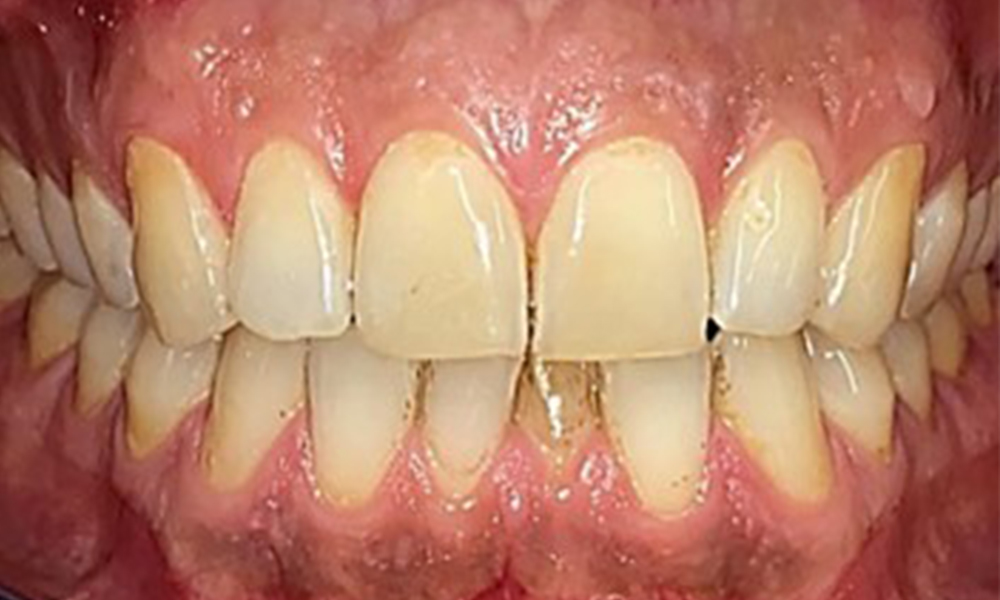

Occlusal view of the maxilla.

Fig. 3: Occlusal view of the maxilla, © Dr R. Krapf

Dental findings

The patient has full dentition with a total of 28 teeth. There were noteworthy erosions and attritions. (Fig. 4, Fig. 5). Due to bruxism, the patient has been wearing a splint with an adjusted bite block at night for many years. The erosions were caused by long-term consumption of isotonic beverages. No periodontal bone loss or active caries were observed.